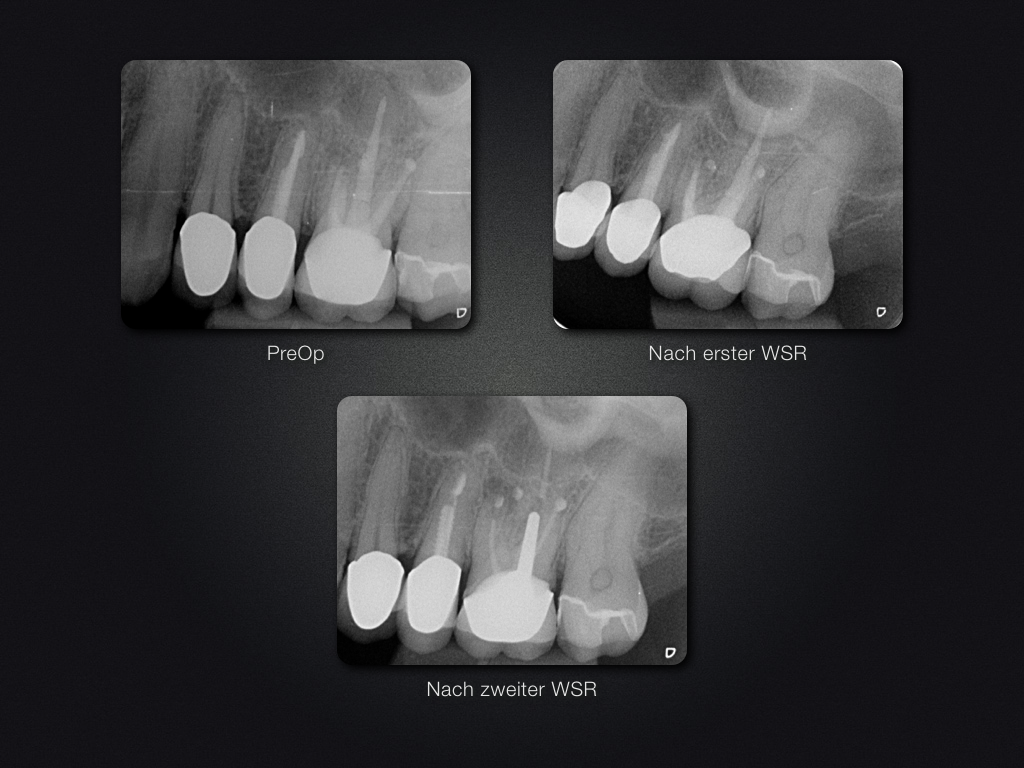

26D.002

2D vs. 3D (XXVI)